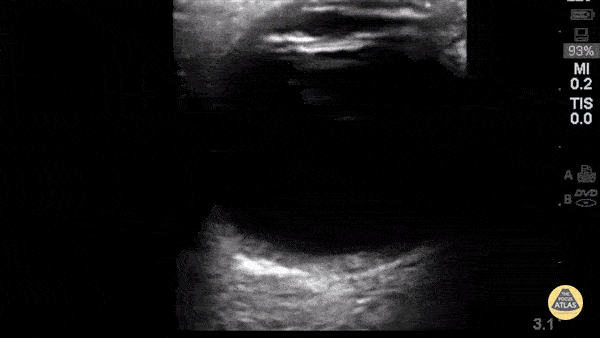

60 year-old woman with longstanding history of severe cataracts presenting 5-months s/p cataract extraction with intraocular lens placement (CEIOL). Ultrasound exam demonstrates a linear echogenic structure posterior to the iris with reverberation artifact in place of normal lenticular structure (native lens) consistent with artificial lens. Image acquired by Robert J. McMickle (Medical Student IV, UCLA) under guidance of Yiju Teresa Liu, M.D., RDMS at Harbor-UCLA Medical Center.